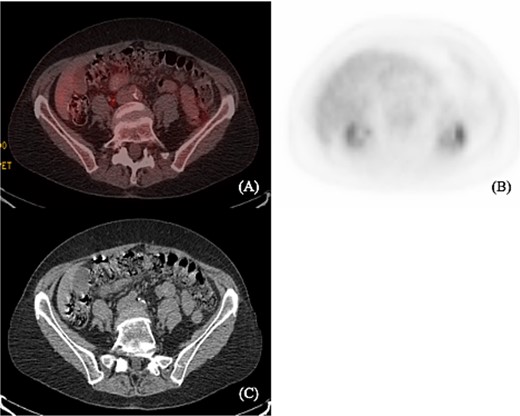

A 75-year-old female with a past medical history of hypothyroidism underwent her first screening colonoscopy. Colonoscopy showed a flat irregular polyp near the splenic flexure of the colon measuring 20 × 40 mm (Fig. 1). The polyp was resected, and biopsy results were consistent with FL grade I. Immunostaining demonstrated positivity to CD20, BCL-2, CD10, and CD21. Ki-67 staining demonstrated a low proliferation index (10%–20%) in lymphoma cells, with a high proliferation index (>90%) in the residual reactive germinal centers (Fig. 2). The lymphoma cells were negative for CD5 and cyclin 1 (Table 1). Other polyps were found in the proximal transverse colon and rectum, and pathology showed sessile serrated adenomas. Subsequently, the patient underwent PET/CT scan in order to estimate further lymphoma involvement. PET/CT scan revealed no evidence of FL nor increased colonic uptake (Fig. 3).

(A) and (B) show axial PET scan sections with 2.2 uptake in the liver. There is no abnormal colonic uptake. Specifically, there is no uptake seen in the splenic flexure corresponding to the mass described on the prior colonoscopy. (C) Computerized tomography shows no mediastinal lymphadenopathy and no axillary lymphadenopathy. Liver and spleen not enlarged. A prominent left inguinal lymph node was noted without evidence of abnormal FDG activity.

PET/CT scan was obtained from the skull to mid-thigh to ensure no further lymphoma involvement. Due to the patient’s resected lesion, no evidence of FL, abnormal colonic uptake, or any uptake in the splenic flexure, which corresponds to the mass on colonoscopy; no further chemotherapy is warranted at this time. The patient underwent a surveillance colonoscopy 6 weeks later, and post-polypectomy scars were biopsied and showed colonic mucosa with mild relative changes and were negative for residual adenomatous changes or lymphoproliferative disorder.